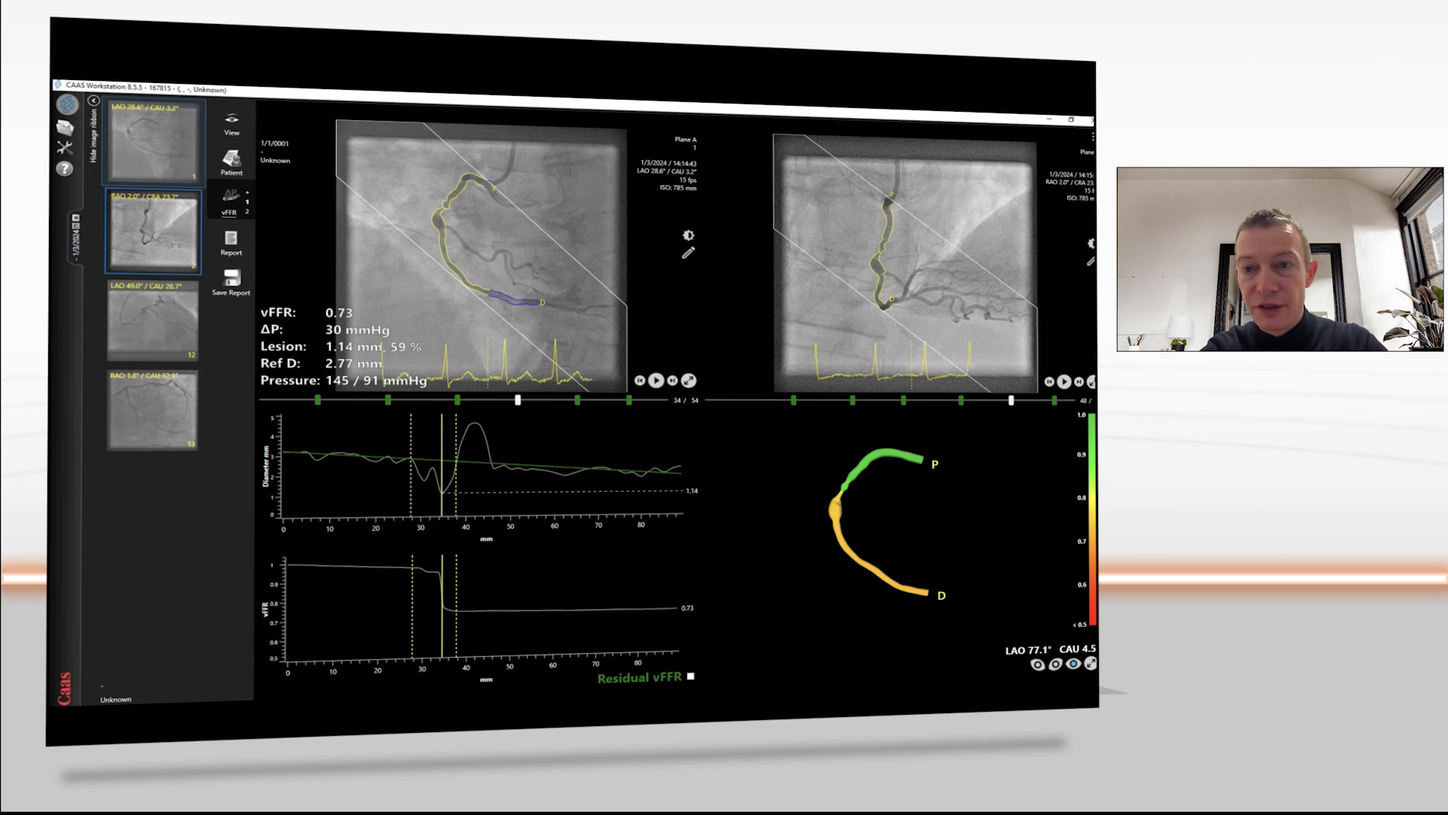

The present and future of vFFR

This online webinar was all about the present and future of vFFR, introducing clinical validation, live cases, and future outlook. Experts Joost Daemen, MD, Professor Eric van Belle, MD, and Kaneshka Masdjedi, MD, discussed the role of angiography-derived physiology CAAS vFFR, how it works, and how you can implement vFFR in your cath lab. Join a live case and experience how pre- and post-PCI vFFR measurement can help in clinical practice. Get more insights into the FAST study validation series and the outcomes of the recently published FAST II multicenter study.

QuantWeb vFFR

Integration of angio-based FFR

Courtesy of University of Tokyo Hospital, Japan

Less invasive angio-based FFR calculation tool vFFR

- calculates the pressure drop in the coronary arteries;

- is a fast and easy-to-use tool to assess the hemodynamic relevance of stenoses;

- shows high correlation with FFR and high inter-observer reproducibility.